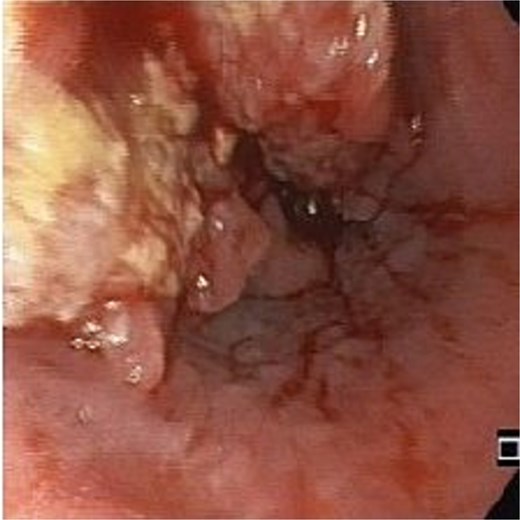

An 83-year-old male with progressive dysphagia and significant weight loss (15 kilograms in 3 months) was diagnosed with locally advanced upper thoracic esophageal squamous cell carcinoma, located 22–26 cm from the incisors, staged as T3N1M0 (Fig. 1). A PEG tube was inserted using the pull technique prior to initiating radiation (50.4 Gy) and chemotherapy (five cycles of Paclitaxel and Carboplatin). Three months after the initial diagnosis, he achieved a complete endoscopic and radiological response and regained the ability to eat orally.